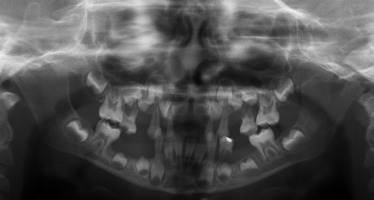

When he was 5 years of age the intraoral examination revealed incomplete primary dentition with five missing teeth, marginal gingivitis, interdental papilla hypertrophy, carious lesions in seven primary teeth, and one permanent tooth of various degrees of advancement for conservative treatment (Fig. 1). The patient was qualified for simultaneous dental treatment under general anesthesia. A panoramic radiograph picture was taken showing the advanced destruction of the alveolar bone in the maxilla and the alveolar part of the mandible. Three primary teeth were completely devoid of bone base. The roots of the lower incisors were only half of their normal length (Fig. 2). Under antibiotic protection (amoxicillin with clavulanic acid at a dose of 30 mg/kg), professional removal of dental plaque and conservative treatment of teeth extraction of four primary teeth with complicated caries and periodontitis were performed. The patient was provided with permanent dental care.